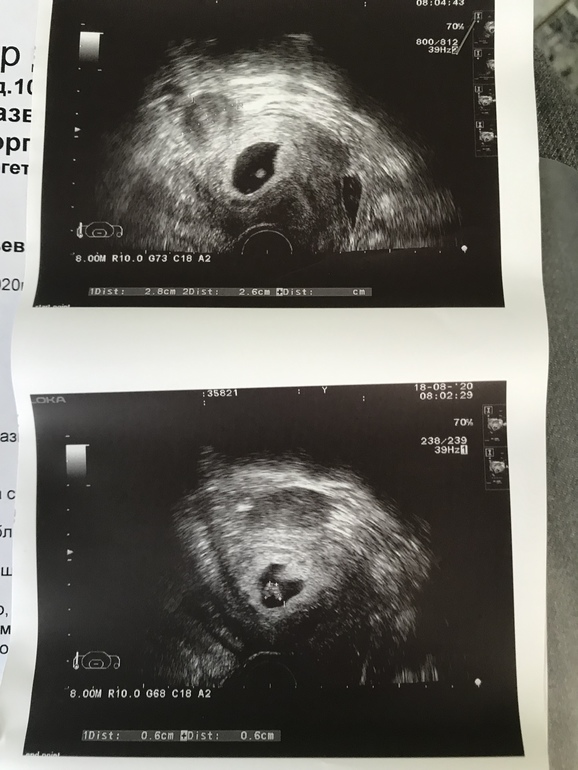

Итак... переносили два эмбриона 4ba и ранняя бласта 2bl. Хгч на 13 дпп 1419. Первое узи на 20 дпп: одно пя и жм. Сегодня пошла на узи 28 дпп: в одном пя два эмбриона!!!!! Сердечки бьются! Все хорошо, все по сроку! Но откуда? У нас в роду ни у кого близнецов не было!!! 😲 и как правильно называется двойня. Я вообще ноль пока в этом вопросе. Очень страшно! Переживаю за малышей

Обновляю: сегодня было узи. Через неделю от того, что описано ниже. Срок 7,3. Аппарат и врач другой. Так вот: она не увидела второго эмбриона!! Как так?!? Он мог рассосаться???? Тот, что виден развивается по сроку. В пятницу направляет меня на экспертное узи искать второго эмбриона!

Всё о нашей беременностиОбновляю: узи 28.08. Все-таки один эмбрион. Смотрело два врача на аппарате экспертного класса.